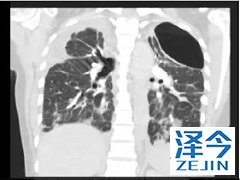

特发性肺纤维化的患者使用尼达尼布有收益吗 特发性肺纤维化属于间质性肺病中的一种,纤维细胞的不断增殖会对患者的呼吸造成影响,如果不进行及时的治疗,患者的平均生存期不会超过三年,而尼达尼布的作用就是在降低肺功能的基础上,缓解疾病的发展,为患者争取更长时间的无进展生存期。

尼达尼布在肺纤维化中的主要临床试验是INPULSIS-1和-2。1在这些试验中,共有638名患者随机接受150 mg 尼达尼布,每日两次,共52周,423名患者服用安慰剂。这些患者的强迫肺活量(FVC)至少是预测值的50%。在INPULSIS-1中,使用安慰剂,FVC下降了239.9 mL /年,使用尼达尼布下降了114.7 mL /年。INPULSIS-2的相应数字分别为207.3毫升/年和113.6毫升/年。使用尼达尼布的肺功能下降幅度较小,具有统计学意义。【乐伐替尼(E7080,Lenvima,仑伐替尼)适应症】(1)分化型甲状腺癌:单药用于局部复发/转移、进展的放射性碘难治性分化型甲状腺癌患者。(2)肾细胞癌:与依维莫司联合用于治疗后进展的肾细胞癌。(3)肝细胞癌。【乐伐替尼(E7080)治疗效果】国内不少患者对E7080的评价不错,尤其是肝癌和胆管癌的患者。大家对这个药物的总体印象是:有效率很高,不少患者的AFP会下降;起效快,大约10-15天可能就会看到效果;剂量和疗效正相关,大部分患者从13mg开始使用,如果无效可以加量到15、17或者20mg ,最高24mg;可以联合用药,比如联合雷利度胺或者184,可以提高有效率;副作用小,大部分患者可以耐受。